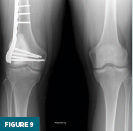

A postoperative radiograph obtained at nearly three months demonstrated the cemented defect in the distal femur with prophylactic plate and screws in appropriate alignment (Figure 9). Continued surveillance with periodic radiographs was recommended for a minimum of two years.